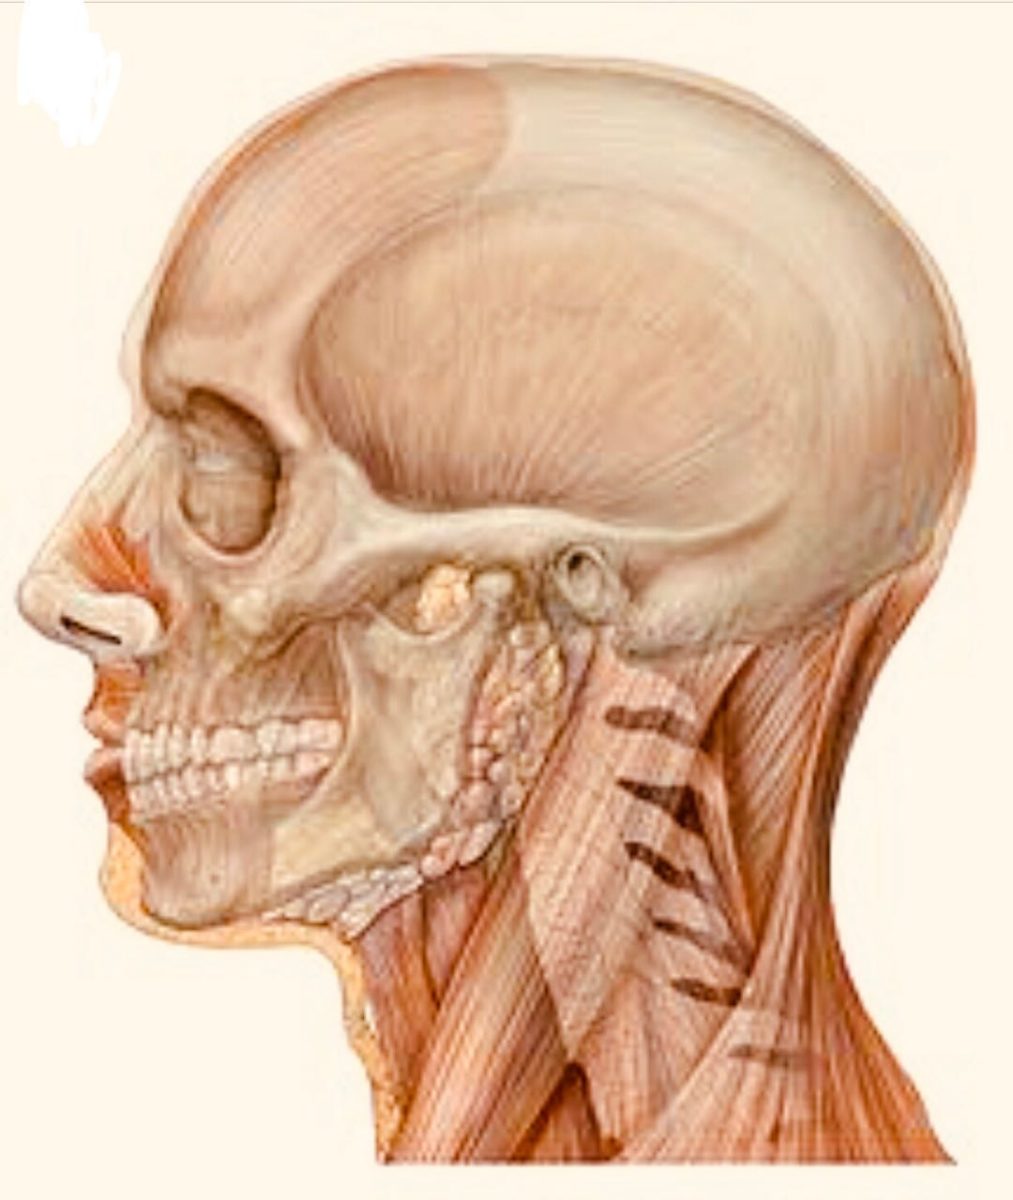

No mundo atual , marcado pelo modismo e imediatismo dos tratamentos odontológicos, muitas vezes a ORTODONTIA tem sido contaminada pela falta de um correto diagnóstico e indicação para o tratamento. O TRATAMENTO ORTODÔNTICO tem em seu principal objetivo a busca pela correta FUNÇÃO do sistema mastigatório, onde a relação maxilo/mandibular e sistema muscular funcionem de […]

Ortodontia é uma especialidade odontológica que corrige a posição dos dentes e dos ossos maxilares posicionados de forma inadequada. Dentes tortos ou dentes que não se encaixam corretamente são difíceis de serem mantidos limpos, podendo ser perdidos precocemente, devido à deterioração e à doença periodontal.